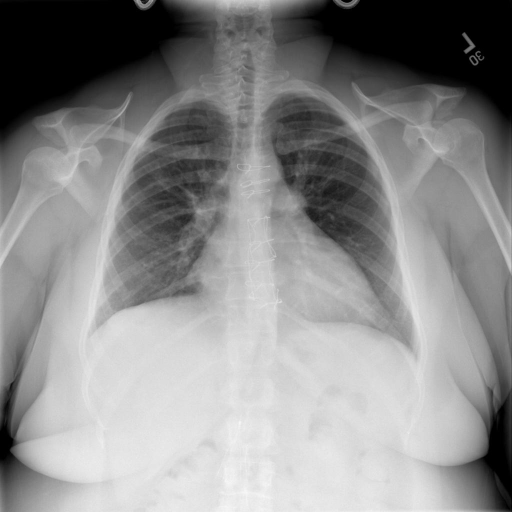

- (1)准备[诊疗报告(中文)](./data/Xray/openi-zh.json)和[X光影像](https://pan.baidu.com/s/13GBsDMKf6xBZBSHpoWH_EA?pwd=k9sh)在`data/Xray`文件夹下; - (2)开始训练: ```bash # 设置CUDA变量,主要是为了解决有时候直接训练而出现无法正确加载到显卡问题 export CUDA_VISIBLE_DEVICES=0,1,2,3 # 开始训练 bash finetune_XrayGLM.sh ``` 这里的复现过程非常简单,主要是很多过程我们都为大家准备好了,大家可以随时复现一个自己的`XrayGLM`。 ### 4.模型训练(通用) ## 效果展示 影像诊断: |X光影像|诊疗报告(医生)|XrayGLM| |:-|:-|:-| |![](./data/Xray/2_1.png)|根据X射线图像,心脏大小正常,肺部看起来很清晰。已经排除了肺炎、积液、水肿、气胸、腺病、结节或肿块的存在。该发现表明一切正常。换句话说,总体印象是胸部正常。|X光片显示,心脏大小正常。肺部没有气胸或胸腔积液的证据。骨骼结构看起来没有任何异常。总的来说,X光片表明没有发现急性心肺疾病的迹象。| |![](./data/Xray/2882_1.png)|X光图片显示没有扭曲的区域、可疑的骨质不透明度或胸腺积液。心脏大小轻微增大,但非常稳定。此外,没有气胸的证据,肺野也正常。总体来说,X光片显示没有急性心脏异常,但要注意轻微的心脏扩大。|X光片显示,心脏大小正常。肺部和纵隔轮廓清晰,没有气胸或胸腔积液的证据。骨骼结构完整,没有任何急性异常。| |![](./data/Xray/2577_1.png)|心影形态在正常范围内。没有急性骨质异常。有可能出现没有明显的吸水或肺实质状况的线索。没有大面积积液或气胸。有可能怀疑其有误吸或肺实质问题。为了确诊和治疗,可能需要进行适当的影像学随访。|心脏大小正常,肺部和纵隔轮廓清晰。没有急性异常或活动受限的证据。没有任何明显的气胸、胸腔积液或肺不张的迹象。此外,也没有发现任何局灶性骨质异常或其他急性疾病。| 多轮对话: |X光影像|诊疗报告(医生)| |:-|:-| |![](./data/Xray/861_1.png)|右侧主动脉突出观察到。心脏大小正常。胸部未发现明显的肺气肿、胸膜积液或可疑的肺部病变。报告指出已知右侧主动脉情况正常。| ```bash >> X光影像路径:./data/Xray/861_1.png >> 用户:这是一张什么图? >> XrayGLM:这张图片显示的是一张肺部检查的X光片。 >> 用户:请描述这张胸部X光片的诊断结果 >> XrayGLM:心脏大小正常,肺部清晰。没有急性心肺疾病的证据。 >> 用户:是否存在肺气肿? >> XrayGLM:没有肺气肿。心脏大小正常,肺部清晰。没有发现急性心肺疾病的证据。 >> 用户:平时饮食该注意什么? >> XrayGLM:饮食应该健康,均衡。建议增加蛋白质的摄入量,因为蛋白质有助于维持肌肉和骨骼的健康。多食用蔬菜、水果、全谷物以及健康的脂肪来源如橄榄油、鱼类等可以帮助获得足够的维生素和矿物质。此外,避免过度饮酒或吸烟,这些习惯可能会对心脏健康产生负面影响。 ``` ## 未来展望 1. 模型的能力更多来源于数据的支持,`OpenI-zh`作为微调数据集,其数据量足以支持研究,在更广泛的任务和性能表现上,我们认为**在大规模数据集上预训练并在高质量少量数据集上微调是一种可行的方案**; 2. 普遍意义的理解上,视觉多模态模型=视觉模型+语言模型。除了需要关注视觉模型信息与语言模型输出的搭配外,还需要**额外关注到语言模型的加强,在人机的对话中,尤其是医疗语言模型的问答上,除了专业的医疗问题回答,带有人文情怀的有温度的回答更应该是我们追寻的目标**。 ## 项目致谢 1. [VisualGLM-6B](https://github.com/THUDM/VisualGLM-6B)为我们提供了基础的代码参考和实现; 2. [MiniGPT-4](https://github.com/Vision-CAIR/MiniGPT-4)为我们这个项目提供了研发思路; 3. ChatGPT生成了高质量的中文版X光检查报告以支持XrayGLM训练; 4. [gpt_academic](https://github.com/binary-husky/gpt_academic)为文档翻译提供了多线程加速; 5. [MedCLIP](https://github.com/RyanWangZf/MedCLIP) 、[BLIP2](https://huggingface.co/docs/transformers/main/model_doc/blip-2) 、[XrayGPT](https://github.com/mbzuai-oryx/XrayGPT) 等工作也有重大的参考意义; ![](./assets/images/mpu.png) 这项工作由[澳门理工大学应用科学学院](https://www.mpu.edu.mo/esca/zh/index.php)硕士生[王荣胜](https://github.com/WangRongsheng) 、[段耀菲](https://github.com/IsBaSO4) 、[李俊蓉](https://github.com/lijunrong0815)完成,指导老师为檀韬副教授、[彭祥佑](http://www.patrickpang.net/)老师。 *特别鸣谢:[USTC-PhD Yongle Luo](https://github.com/kaixindelele) 提供了有3000美金的OpenAI账号,帮助我们完成大量的X光报告翻译工作 ## 免责声明 本项目相关资源仅供学术研究之用,严禁用于商业用途。使用涉及第三方代码的部分时,请严格遵循相应的开源协议。模型生成的内容受模型计算、随机性和量化精度损失等因素影响,本项目无法对其准确性作出保证。即使本项目模型输出符合医学事实,也不能被用作实际医学诊断的依据。对于模型输出的任何内容,本项目不承担任何法律责任,亦不对因使用相关资源和输出结果而可能产生的任何损失承担责任。 ## 项目引用 如果你使用了本项目的模型,数据或者代码,请声明引用: ```bash @misc{wang2023XrayGLM, title={XrayGLM: The first Chinese Medical Multimodal Model that Chest Radiographs Summarization}, author={Rongsheng Wang, Yaofei Duan, Junrong Li, Patrick Pang and Tao Tan}, year={2023}, publisher = {GitHub}, journal = {GitHub repository}, howpublished = {\url{https://github.com/WangRongsheng/XrayGLM}}, } ``` ## 使用许可 此存储库遵循[CC BY-NC-SA](https://creativecommons.org/licenses/by-nc-sa/4.0/) ,请参阅许可条款。